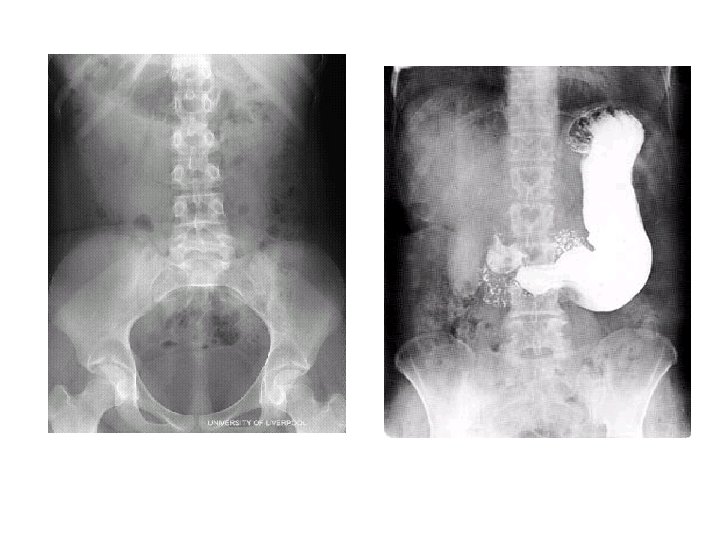

Fluoroscopy 22

TECHNOLOGIST • FLUOROSCOPY • Dawn Charman RT (R), (F) • CONTRAST MEDIA (X-RAY DYE)